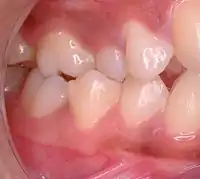

| Malocclusion in 10-year-old girl | |

In orthodontics, a malocclusion is a misalignment or incorrect relation between the teeth of the upper and lower dental arches when they approach each other as the jaws close. The English-language term dates from 1864;[1] Edward Angle (1855-1930), the "father of modern orthodontics",[2][3] popularised it. The word "malocclusion" derives from occlusion, and refers to the manner in which opposing teeth meet (mal- + occlusion = "incorrect closure").